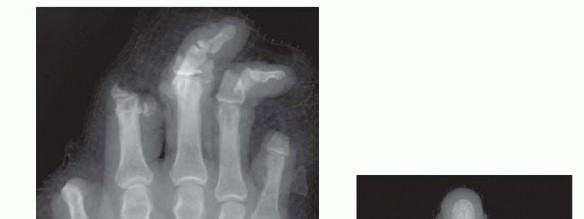

When the patient arrives in the emergency department, standard radiographs of the amputated parts and the injured limb are obtained (FIG 4).Laboratory evaluations should include a complete blood count, basic metabolic panel, coagulation panel, drug screen, and blood type and crossmatch. Other preoperative tests are ordered as indicated by the patient's age and comorbidities.

FIG 4 • A. Standard posteroanterior (PA) radiograph of the injured hand. B. A radiograph of the amputated parts is also obtained by placing the bag containing the parts directly on the x-ray cassette.